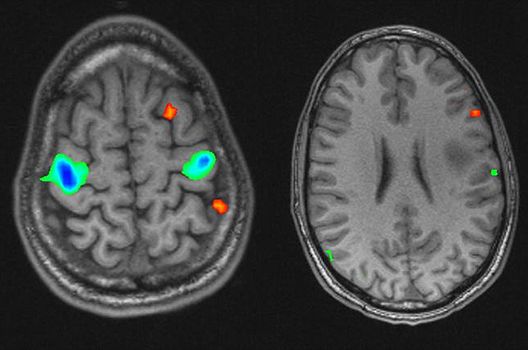

Die Schwerpunkte in der MR-Forschung liegen in der multiparametrischen und funktionellen Bildgebung bei onkologischen und anderen, neuroradiologischen Fragestellungen und umfassen die Anwendung modernster MR-Verfahren sowie die Untersuchung an Hochfeld-Geräten.

Die Magnetresonanztomographie (MRT) ist ein Verfahren, bei dem durch magnetische Kräfte Bilder des Körperinneren angefertigt werden. In der Neuroradiologie können manchmal kleinste Veränderungen schwere Folgen haben; daher forschen wir an der Entwicklung hochauflösender MRT-Sequenzen, mit denen diese Prozesse und auch einzelne Nervenfaserbahnen sichtbar gemacht werden können. Darüber hinaus sind bei vielen Erkrankungen des Gehirns die Blutgefäße betroffen. Daher arbeiten wir an der Neu- und Weiterentwicklung von MRT-Sequenzen zur Darstellung der Blutgefäße und zur Blutflussanalyse (sog. „Angio-MRT“). Einen besonderen Forschungsschwerpunkt unserer Klinik stellen die MR-Protonenspektroskopie und die funktionelle MRT dar, mit denen die Analyse einzelner chemischer Substanzen im Hirngewebe oder die Darstellung ausgewählter Hirnfunktionen möglich ist.